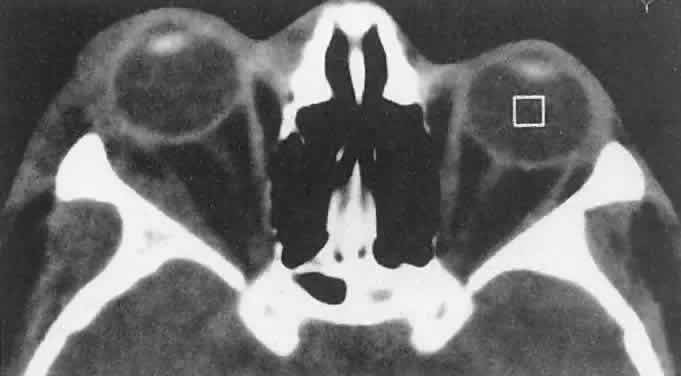

Dermoid cysts are most often encountered at the frontozygomatic articulation but can occur at other suture lines, including those deep in the orbit. Most lesions are anterior and paraorbital (Fig. 19), located between the orbicularis muscle and the periosteum overlying the orbital rim, and have a fibrous stalk to the suture line. Anterior cysts produce minimal bone change. Other lesions may be entirely intraorbital, causing proptosis and globe displacement. Their expansion produces an overall increase in orbital volume as well as local bone changes (Fig. 20). Dermoid and epidermoid cysts also may be largely intradiploic, with expansion into the anterior cranial fossa, the temporal fossa, or the orbit. Dumbbell lesions may be present with narrow intraosseous components.

Fig. 20. A. Right proptosis was noted only a few weeks before presentation in this 3-year-old girl. B. A long-standing process is suggested by overall expansion of the bony orbit and local fossas on the orbital faces of the zygomatic and sphenoid bones. Keratin clumps and glandular products within the dermoid cyst have different radiodensities.

Anterior, paraorbital dermoid cysts usually are evident soon after birth. Deeper lesions may not declare themselves until mid- or late childhood, or even the adult years. Expansion of the cysts generally is slow and linear, reflecting continuous desquamation of keratinizing epithelium. There may be a point at which the pressure within the cyst inhibits further proliferation and sloughing of epithelial cells, accounting for the clinically observed stability of many lesions. Sporadic enlargement may be caused by hormonally influenced sebaceous gland secretion or by rupture of the cyst wall with a granulomatous inflammatory response to the cyst contents (see Figs. 19B-D). Such episodic change in an otherwise gradual growth pattern places intraorbital dermoid cysts into the current differential diagnosis.

Anterior lesions generally are diagnosed and removed without difficulty, although their occasional occurrence near the lacrimal excretory system can complicate treatment.89 Surgeons should strive for excision of an intact cyst, because residual epithelial elements can lead to recurrence. CT examination of deeper lesions discloses a cystic mass with some internal heterogeneity caused by the different radiodensities of keratin clumps and oily secretions (see Fig. 20B). Bone changes, from shallow fossas to spherical defects, are smooth, with a sclerotic margin and a punched-out appearance. Based on the CT findings, the differential diagnosis includes cholesterol granuloma and unifocal eosinophilic granuloma. Superomedial orbital dermoid cysts must be distinguished from meningoencephaloceles before surgical intervention.